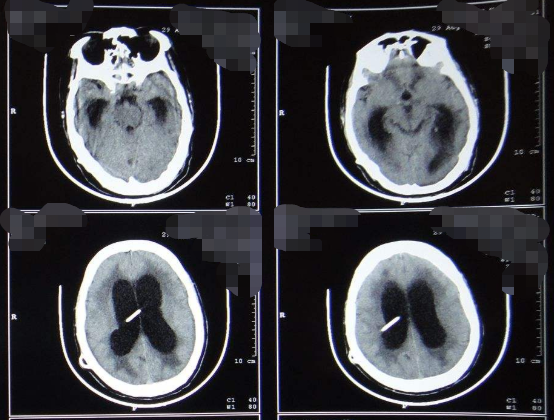

什么是脑积水?INC国际神经外科指出,脑积水是指由于脑脊液循环受阻、吸收障碍或分泌过多,使脑脊液大量积聚于脑室系统或蛛网膜下隙,导致脑室或蛛网膜下隙扩大,引起头颅扩大、颅内压增高和脑功能障碍,脑积水可分为两大类——非交通性脑积水和交通性脑积水。

脑积水能治好吗?采用内镜电凝烧灼双侧脑室脉络丛,为治疗脑积水的传统方法。此方法通过减少脉络丛的脑脊液分泌,达到缓解脑积水目的。Pople等(1995)报告36例手术后长期随访,症状稳定者占64%。

哪些人群适合使用脑积水侧脑室脉络丛内镜电凝术?其实,症状缓慢发展的交通性脑积水以及采用脑室-腹腔(V-P)分流术无效者都适用该手术,脑室内感染者。非交通性脑积水多选用其他方法。